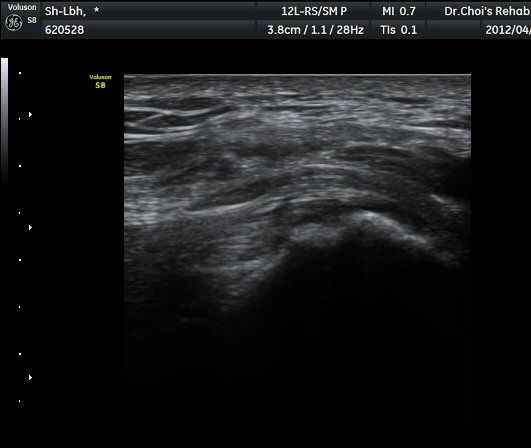

ÃÊÀ½ÆÄ °Ë»ç

´ëÀüÀÚ(gtreater trochanter) ¾ÕºÎºÐ Ⱦ´Ü¸é °Ë»ç¿¡¼­ ´ëÀüÀÚ Ç¥Ãþ¿¡ ¼ÒµÐ±ÙÀÌ °í¿¡ÄÚ ¼¶À¯¾ç ¸ð¾çÀ¸·Î °üÂûµÇ°í ¼ÒµÐ±Ù°ú Àå°æÀÎ´ë »çÀÌ¿¡ ¾à 2mm µÎ²²ÀÇ Á¤¾×³¶ ºÎÁ¾ÀÌ °üÂûµÈ´Ù(±×¸² 1, ³ë¶õ»ö È­»ìÇ¥) . ŽÃËÀÚ¸¦ µÚÂÊÀ¸·Î À̵¿ÇÏ¿© Áߵб٠ÈûÁÙÀÌ °üÂûµÇ°í Áߵб٠ÈûÁÙ ºÎÂøºÎ ÀϺο¡ ¹«¿¡ÄÚ ¿¬°á¼º ¼Ò½ÇÀÌ °üÂûµÇ°í ±× Ç¥Ãþ¿¡µµ Á¡¾×³¶ÀÇ ºÎÁ¾ÀÌ °üÂûµÈ´Ù(±×¸² 2). ȯÀÚÀÇ µÚÂÊ¿¡¼­ ÃÊÀ½ÆÄ À¯µµÇÏ ÁÖ»çÄ¡·á¸¦ À§ÇØ ºñ½ºµëÇÑ È¾´Ü¸é°Ë»ç¿¡¼­ ´ëµÐ±Ù